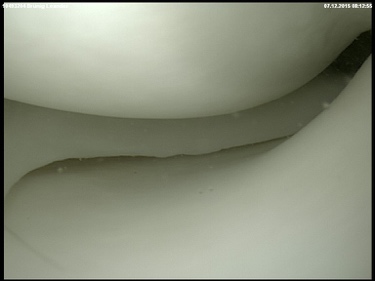

Intact meniscus

The inner and outer meniscus serve to buffer the load and stabilise the joint. Damage to the meniscus can occur due to accidents, or wear and tear, or a combination of both. The consequences are pain, swelling, and possibly also entrapment. Meniscus damage occurs most frequently between the ages of 30 and 50. Men are affected twice as often as women (9 to 4.2/10000 respectively). If the damage is symptomatic, it can be repaired minimally-invasively by arthroscopy. The follow-up treatment depends on whether parts of the meniscus were removed (pain-adapted full weight-bearing) or whether the meniscus was sutured (usually partial weight-bearing). Unfortunately, only a few meniscus tears are suitable for suturing.